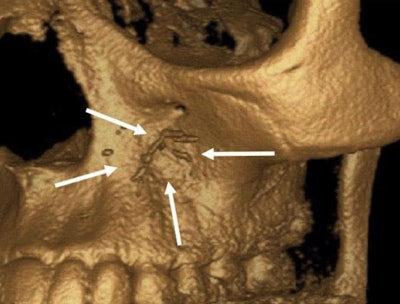

At the endodontic department, she underwent a clinical exam and imaging. A CBCT scan showed dislocation of opaque material from the canals of tooth #14 to the floor of the left maxillary sinus, posterior superior alveolar artery, infraorbital artery, and the area of the infraorbital foramen.